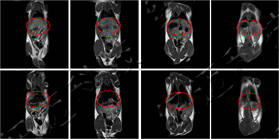

儀器使用小動物核磁共振成像系統,圖像為T1加權像橫斷面、冠狀面,采樣參數如下:FOV=100mm×100mm, TR=400ms, TE=19ms, 層厚3.5mm, 層間距1mm, 累加次數16, K空間大小192×256。成像結果顯示,注射造影劑后,大鼠心臟與肝臟變亮,且隨代謝時間延長逐漸變暗。

大鼠造影前后MRI冠狀面

大鼠體內造影劑代謝MRI橫斷面